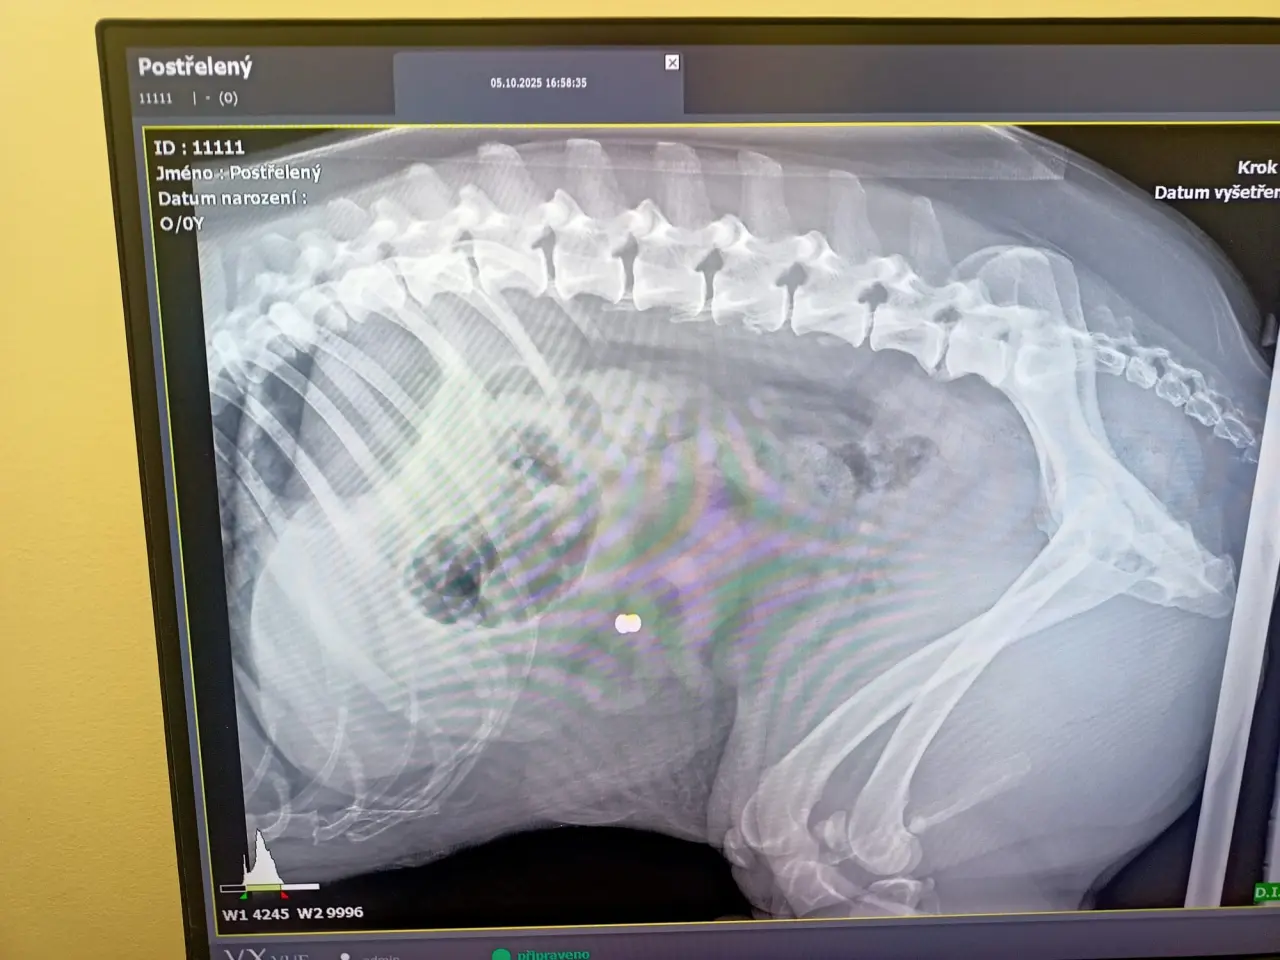

🐾 Rey děkuje z celého srdce! 💖

Komu pomůžeme?